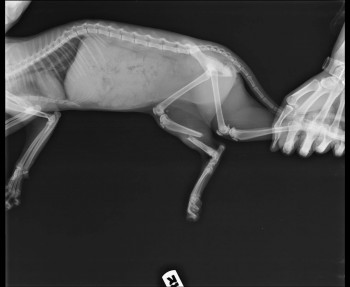

Вкратце: операцию провели, от наркоза кошка отходила очень долго и громко. Наверное в это время и сместила немного кость. Вот снимки через два дня после операции.